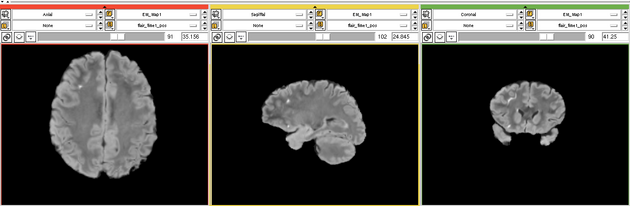

| − | Image: | + | Image:EMS LesionExp T1.png |

| − | Image: | + | Image:EMS LesionExp FLAIR.png |

Two channel automatic segmentation of T1 and FLAIR MRI brain scans into the major tissue classes (gray matter, white matter, csf). The pipeline consist of the following steps: